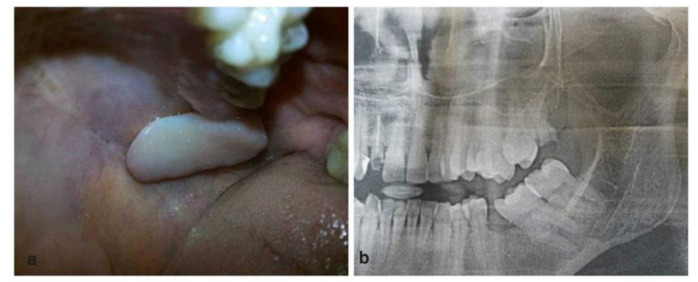

神经鞘瘤被认为是起源于雪旺细胞的良性软组织肿瘤。口腔神经鞘瘤很少见,仅占所有神经鞘瘤的1%。细胞性神经鞘瘤(CS)是一种罕见的神经鞘瘤的组织学变异,其特点是高细胞性和细胞异型性。我们报告一例腭黏膜局部生长的病例,在组织病理学检查上模仿恶性周围神经鞘瘤(MPNST)的特征;通过临床、组织病理学和免疫组织化学特征的相关性,将其与MPNST区分开来。

Schwannomas are considered benign soft tissue tumors that originate from Schwann cells. Oral Schwannomas are rare and account for only 1% of all Schwannomas. Cellularschwannoma (CS) is a rare histological variant of schwannoma, characterized by high cellularity and cellular atypia. We present a case of localized growth of palatal mucosa that imitated the features of malignant peripheral nerve sheath tumor (MPNST) on histopathological examination; it was differentiated from MPNST by the correlation of clinical, histopathological, and immunohistochemical features.